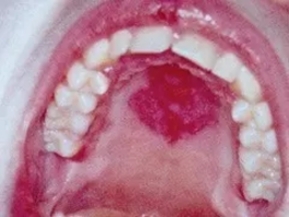

图为干燥综合征小唾液腺淋巴浸润的内镜下表现与组织病理学图像

消化系统改变:口干、吞噬困难(75%)、食管运动异常(36%)、萎缩性胃炎(钡餐或可有胃癌征象)、肝大(8%—23%,可有肝酶异常、肝脏淋巴细胞浸润),胰腺分泌功能下降(可有血浆胰蛋白酶、淀粉酶、脂肪酶升高)。